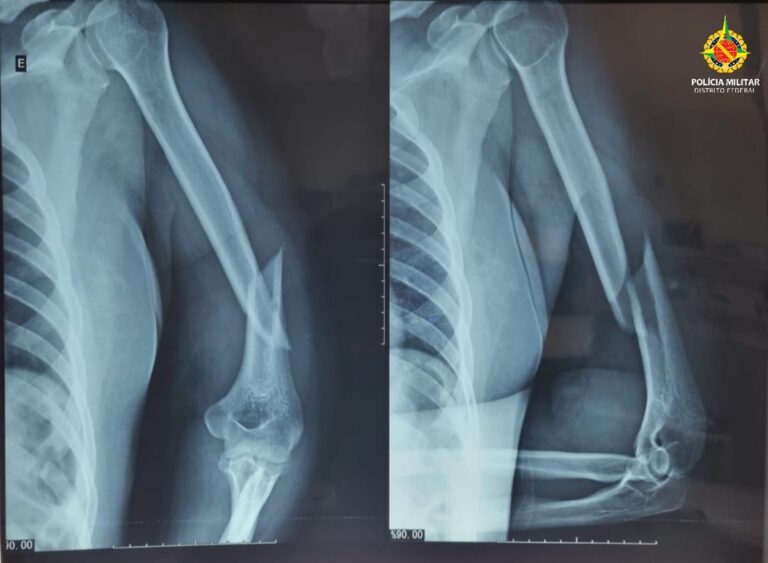

A agressão foi descoberta depois que vizinhos ouviram os pedidos de socorro e acionaram a polícia. No local, os policiais encontraram a mulher com hematomas no rosto, inchaço ao redor dos olhos, sangramento nos ouvidos, fratura no úmero esquerdo e luxação no ombro. Além disso, o quadro clínico indicava traumatismo cranioencefálico.

A vítima foi encaminhada ao Hospital Regional de Taguatinga (HRT), onde permanece internada aguardando procedimentos cirúrgicos.